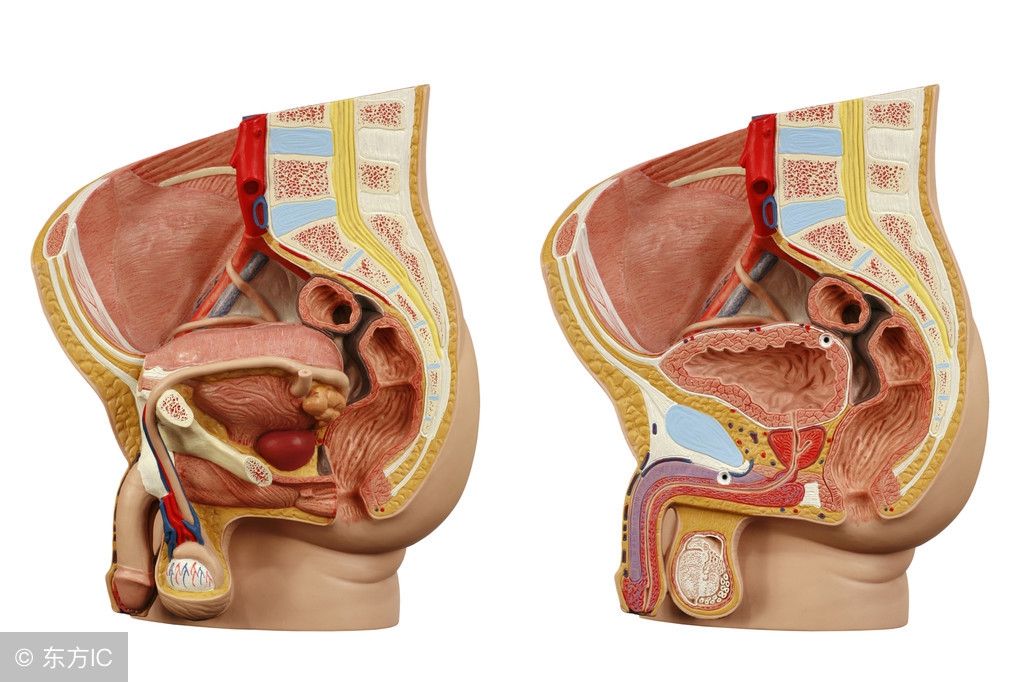

部分正常女性在月经期或排卵期会有少量的盆腔积液。这是因为在解剖上盆腔处于腹腔最低的部位,当盆腹腔脏器有少量渗出液、漏出液或破裂出血时,液体会首先聚积在盆腔,从而形成盆腔积液。如月经时,少量经血逆流至盆腔可造成盆腔积液;月经中期排卵时的卵泡液积在盆腔也可导致盆腔积液;便秘的患者,由于肠蠕动不正常,可引起少量肠液渗出导致盆腔积液。

其他:卵巢及输卵管肿瘤、肝肾疾病均可引起盆腔积液同时伴有腹水,甚至胸水。异位妊娠和黄体破裂可引起盆腔血性积液。结核性盆腔炎时,腹膜及盆腔脏器表面布满粟粒状结核病灶,会产生大量的渗出液聚积在盆腔。

月经紊乱:倘若患者盆腔内有瘀血,月经量可能变多;倘若病症已经影响卵巢功能,可能造成月经失调;倘若患者已出现输卵管阻滞,可致不孕。

不孕:不孕是盆腔积液最常见的病症之一,这是因为盆腔积液容易造成患者输卵管堵塞。临床表现为子宫后移,子宫活动受限,或输卵管粘连。